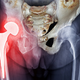

Članek predstavlja sodobne pristope zdravljenja z matičnimi celicami v ortopediji. izr. prof. dr. Mohsen Hussein, dr. med., spec. ortopedije, svetnik V razvoju ortopedije lahko izpostavimo tri velike mejnike. Prvi je … · Delo · 1t

poškodbe hrustanca mezenhimske matične celice orthobiologics matične celice v ortopediji biološke terapije artroza zdravljenje z matičnimi celicami promo poškodbe mišic regenerativna medicina artros objavi tvitaj